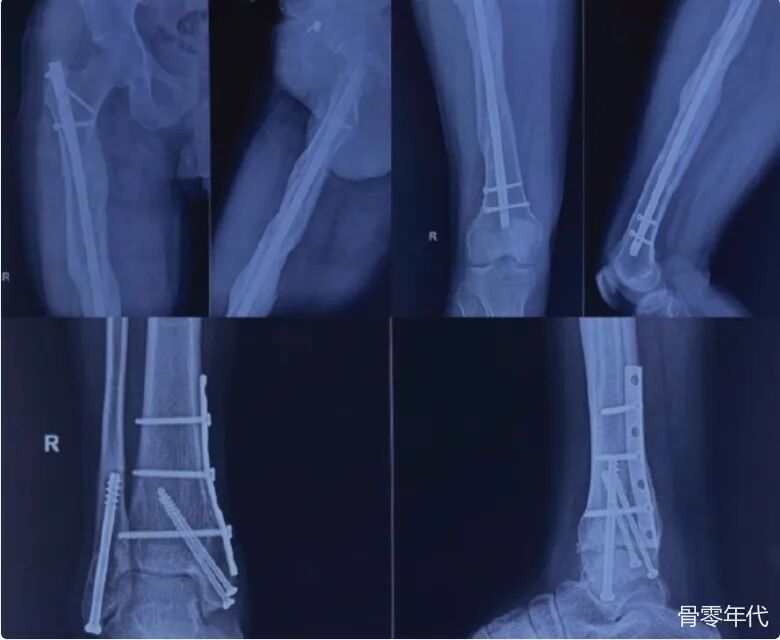

影像学表现